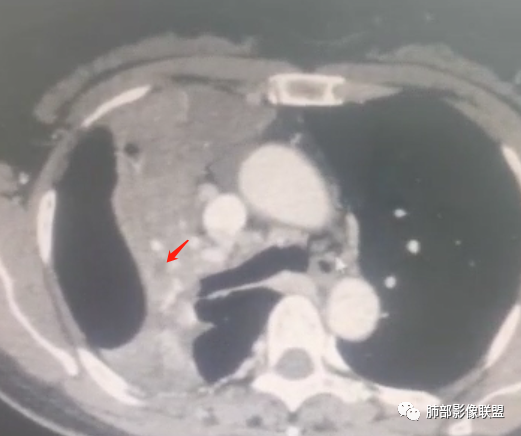

右肺上叶实变,宽基底与胸膜相连,邻近胸膜积液,上叶支气管阻塞,不均匀强化,血管显示可,局部坏死环形强化,可见气泡,考虑慢性炎症伴脓肿,放线菌?鉴别腺癌

右肺上叶尖段大片状实变,近肺门侧支气管闭塞,并可见病灶内部有片状液化坏死区,有空泡气体,病灶紧贴胸膜,胸膜反应性增厚,伴有少见积液,增强扫描内部不均匀强化,血管走形正常。影像符合慢性化脓性感染。

右肺上叶大片实变影,内密度不均匀,可见坏死环形强化,支气管被粘液栓阻塞,首先考虑感染性病变,奴卡?放线菌感染?

右肺上叶大片实变,密度不均,近端环形强化并见空泡,病灶与胸膜广基相连,之间并可见积液,考虑放线菌,鉴别腺癌

晨读:右肺上叶实变,密度欠均匀,不均匀强化,内血管走形可,近端环形强化并见空泡,考虑放线菌可能,鉴别腺癌

右主支气管周围多发淋巴结肿大融合(提示右主支气管有外受压变窄),右肺上叶尖前不张,内见支气管粘液栓和坏死及环形强化特点,邻近胸膜增厚及右肺上叶后段支气管扭曲及狭窄后扩张,周边索条纤维化,综合TB表现,超声支气管镜检查。

右肺门结节,显著强化,内可见坏死及悬浮气泡,远端阻塞性肺不张,心脏纵隔右移,结节及不张内血管影走行自然,并可见粘液拴,隆突下淋巴结肿大,慢性病程,病变跨叶,首选感染性病变放线菌感染,其次鉴别腺癌

有脓腔,内壁光滑、强化环——支持感染

远端是不张合并感染

肺放线菌病

放线菌病